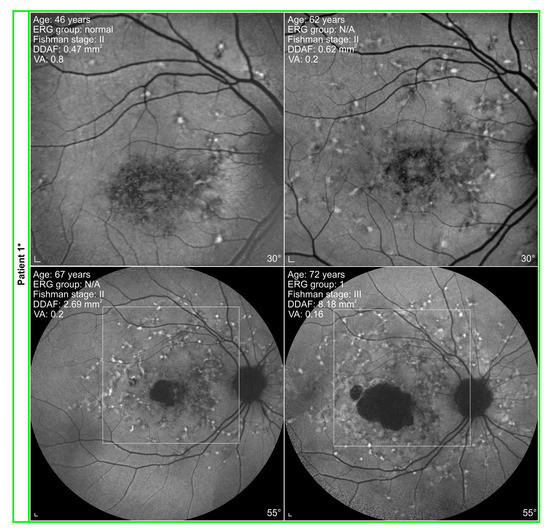

3.2. Electrophysiological and Fundus Autofluorescence Progression

4.2. Progression of Definitely Decreased Autofluorescence Area